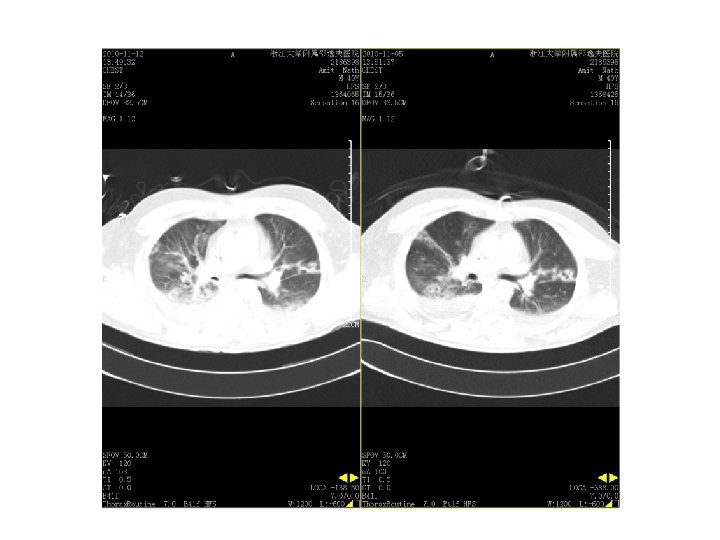

11. 12 vs 11. 5

2010. 9. 13复查CT